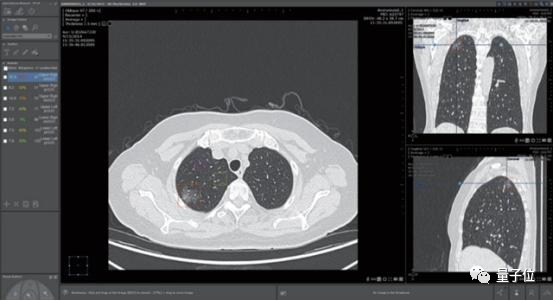

医疗影像辅助诊断是当时医疗AI公司扎堆投入的领域。这家公司最大的卖点肺结节诊断,则是红海中的红海。

一家医院接入4、5家AI肺结节诊断产品成了司空见惯,曾有影像医师笑称:

中国人的肺结节都不够用了。